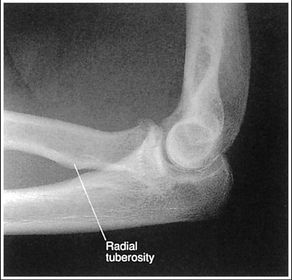

| Lateral Elbow | The elbow is elevated above the level of the shoulder radial head anterior to coronoid - should be superimposed capitulum too proximal to trochlea radial tuberosity seen - hand is pronated |

| Lateral Elbow | Elbow is depressed below the level of the shoulder radial head superimposed by coronoid capitulum too distal to medial trochlea |

| Lateral Elbow | the distal wrist is elevated hand is pronated because you can see the radial tuberosity - should not see that |

| Lateral Elbow Evaluation Criteria | ANATOMY: distal humerus, proximal forearm, entire elbow joint CRITERIA: humeral epicondyles are superimposed radial tuberosity is invisible (if visible the hand is pronated) half of the radial head superimposed by coronoid process Elbow is flexed 90 degrees to see/not see fad pads 3 concentric arcs visible POSITIONING: CR perpendicular @ lateral epicondyle |